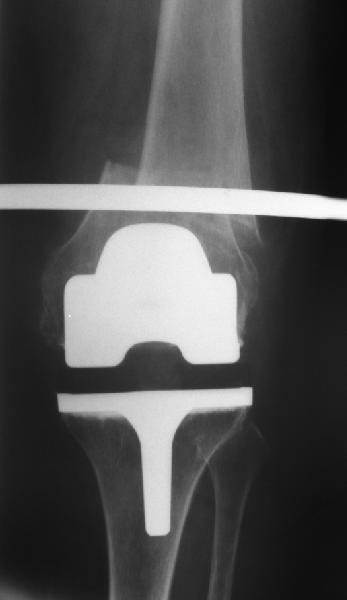

Поступила больная с перипротезным переломом

Перипротезный перелом у пациентки 67 лет . Эндопротезирование год назад . Сопутствующие нарушения ритма сердца и вес 120 кг при росте 185 .Думаю о мыщелковой пластинке с угловой стабильностью рыбинского исполнения остальное больной не потянуть . Заранее всем спасибо !

Уважаемый, Игорь! То что демонсрирует Александр Николаевич, высший пилотаж "neilinga" В нашей стране выполяется единичными спциалистами. Поэтому если не владеете методикой лучше пригласить к себе Челнокова. в случае накостного остеосинтеза, за который говорит ожирение и сопутствующая патология, не используте пластину Рыбинска. она не правильно предмоделирована и невесть из какого металла выполнена.поэтому неизвестно когда сломается при осевой нагрузке, и, кроме того,вы заведомо создадите вальгусную дефомацию, что повлечет за собой расшатывание компонентов. оптимальна в данном случае пластина "Synthes" скоминированными отверстиями. точно титан, идеально предмоделироана, винты надежно блокируются в отверстиях в отличие от Рыбинска.оперировать необходимо на спицевом дистракторе, спицы проводить перпендикулярно оси отломков. после репозиции под онтролем ЭОП чере два доступа пластину максимальной длины.дистальн заблокировать не менее 6 отверстий, проксимально-5.если нет возможности выполнить предложнные варианты, лучше пациентку перевести в отделение высшего уровня.Слишком высоки ставки. С уважением, Сергей.